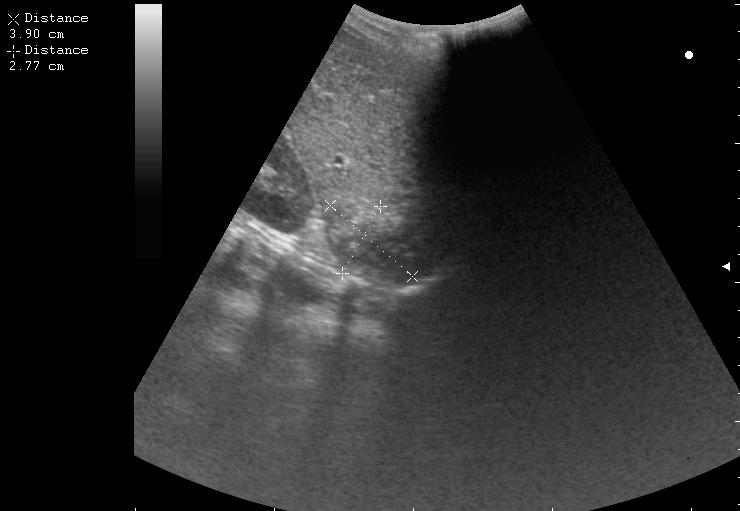

железный дрын вошел в правую подвздошную область, остановился в капсуле печени.

наезд большой черной Прады на маленькую (13кг) 5-летнюю девочку.

получает Медаксон, рабочая версия - изменение желчного пузыря вследствии травмы (шепотом - рекомендация хирургу сменить антибиотик)

сегодня был селезёночный день.